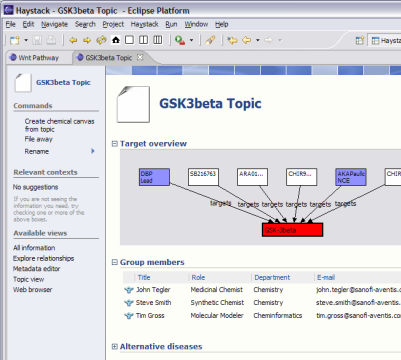

BioDASH is a Semantic Web prototype of a Drug Development Dashboard that associates disease, compounds, drug progression stages, molecular biology, and pathway knowledge for a team of users. It is based on the concept of a therapeutic topic model, something that exists in one form or another within the pharmaceutical industry. Since such relevant information usually resides across many intranet database servers and different R&D groups, the challenge is more about leveraging the information one already has in a semantically coherent fashion than about making new data models.

The demonstration focuses on an investigation into the therapeutic value of GSK3beta (glycogen synthase kinase 3 beta), a regulatory enzyme associated with multiple diseases, including diabetes type 2 as well as Alzheimer’s. Several screened compounds are known antagonists of GSK3beta and are available. GSK3beta participates in a variety of important pathways (WNT, Insulin Receptor Singalling), but little is known about the exact roles these play in different tissues, or how they work together. [more on GSK3 beta…]

The BioDASH demonstration is built on Haystack, which is an extensible Semantic Web Browser developed by the Haystack research group at the MIT Computer Science and Artificial Intelligence Laboratory. Haystack is a plug-in for the Eclipse platform and runs on Windows, Linux, and Mac OS X. More information on the use of Semantic Web Browsers in life sciences applications can be found here.

In the BioDASH demo, information is provided about drug targets and compounds (public sources), which are linked together in the context of a disease topic and a team (see GSK3beta.rdf). A data model is presented that maps Compounds to their drug development role (ChemicalEntities):

Common biological knowledge is attached to Gene entities, while knowledge specific to target identification, validation, therapeutic mechanisms, compound interactions, and toxic side-effects are associated with a Target. Both Compounds and Chemical Entities can “target” a Gene Target (see above figure). This allows the aggregation and viewing of putative drug relations between a target and any set of compounds, merged from in-house drug development projects, academic research, or competitors.